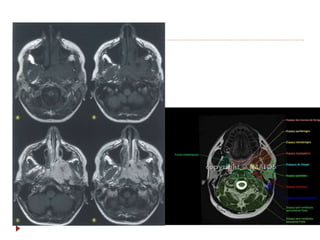

 TC contrastada é o método de escolha (1-3 mm).

 RM  T1, T2, STIR, gadolíneo, supressão de

gordura, difusão.

Nasofaringe  TC contrastadaé o método de escolha (1-3 mm).  RM  T1, T2, STIR, gadolíneo, supressão de gordura, difusão.